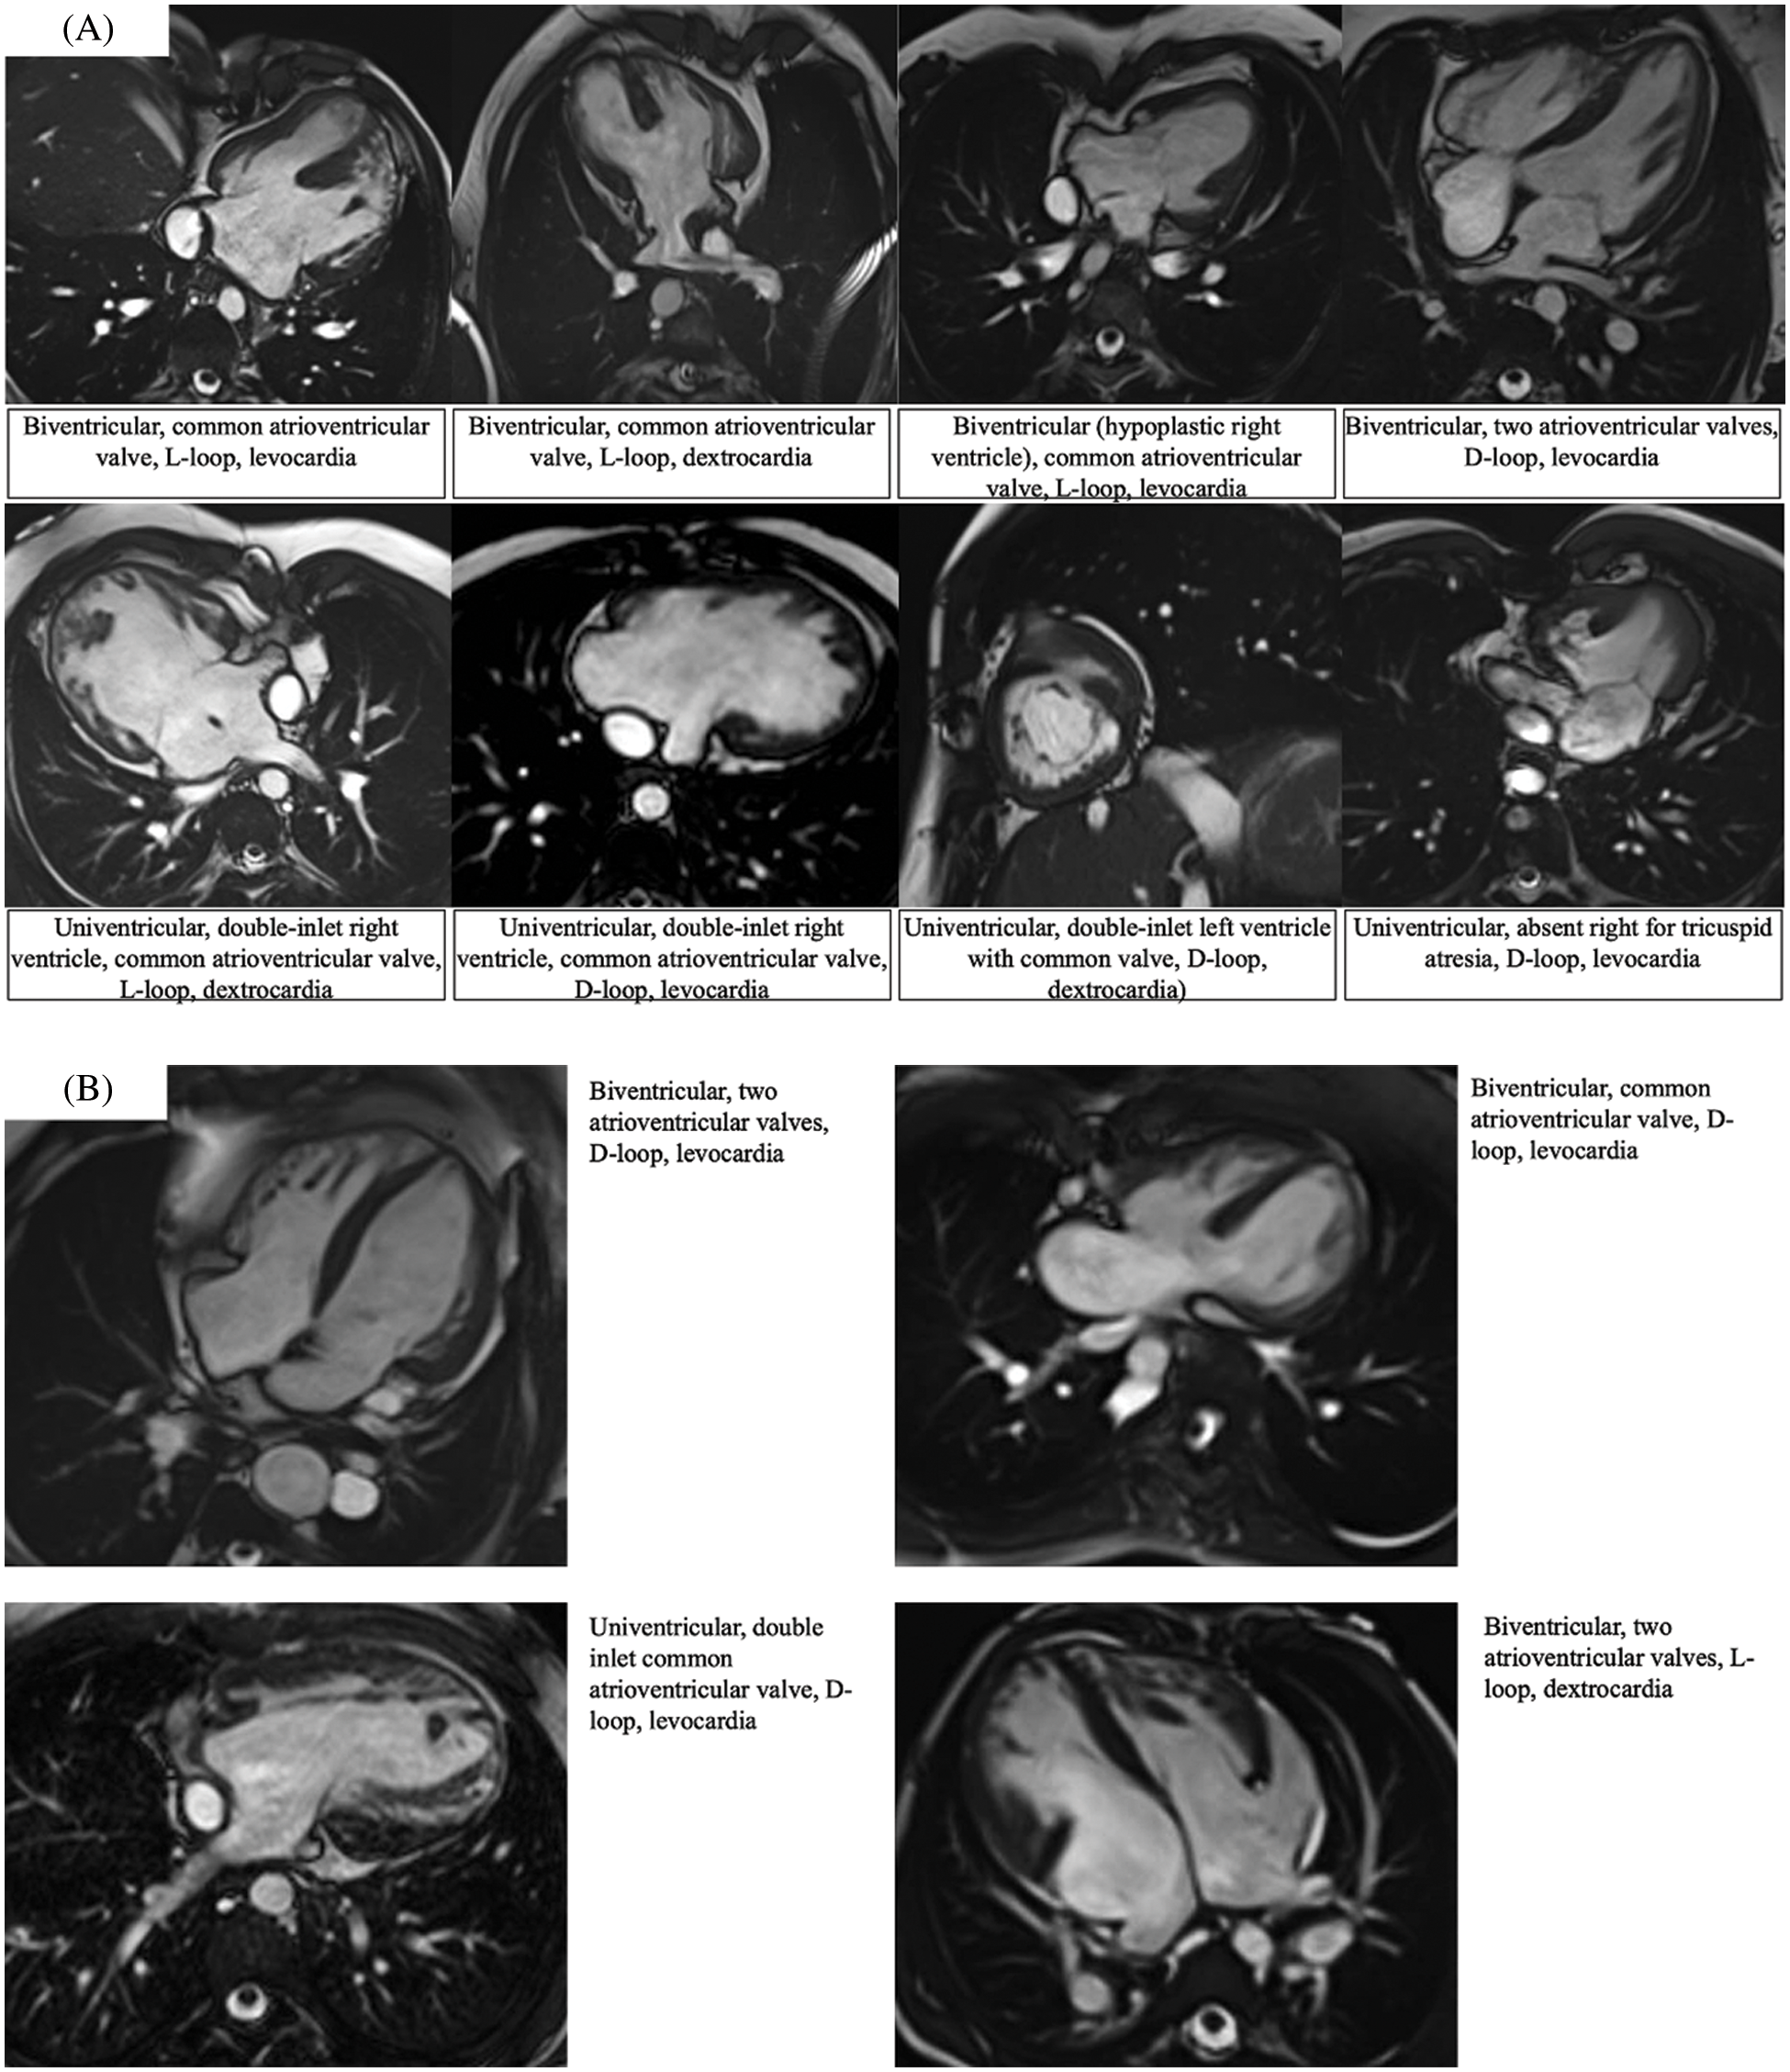

Figure 6: Magnetic resonance imaging showing the different atrioventricular connections as observed in right {Panel A} vs. left {Panel B} isomerism. Each panel is supported by a short description